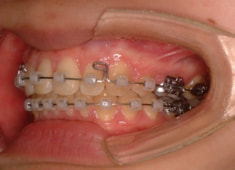

治療開始時